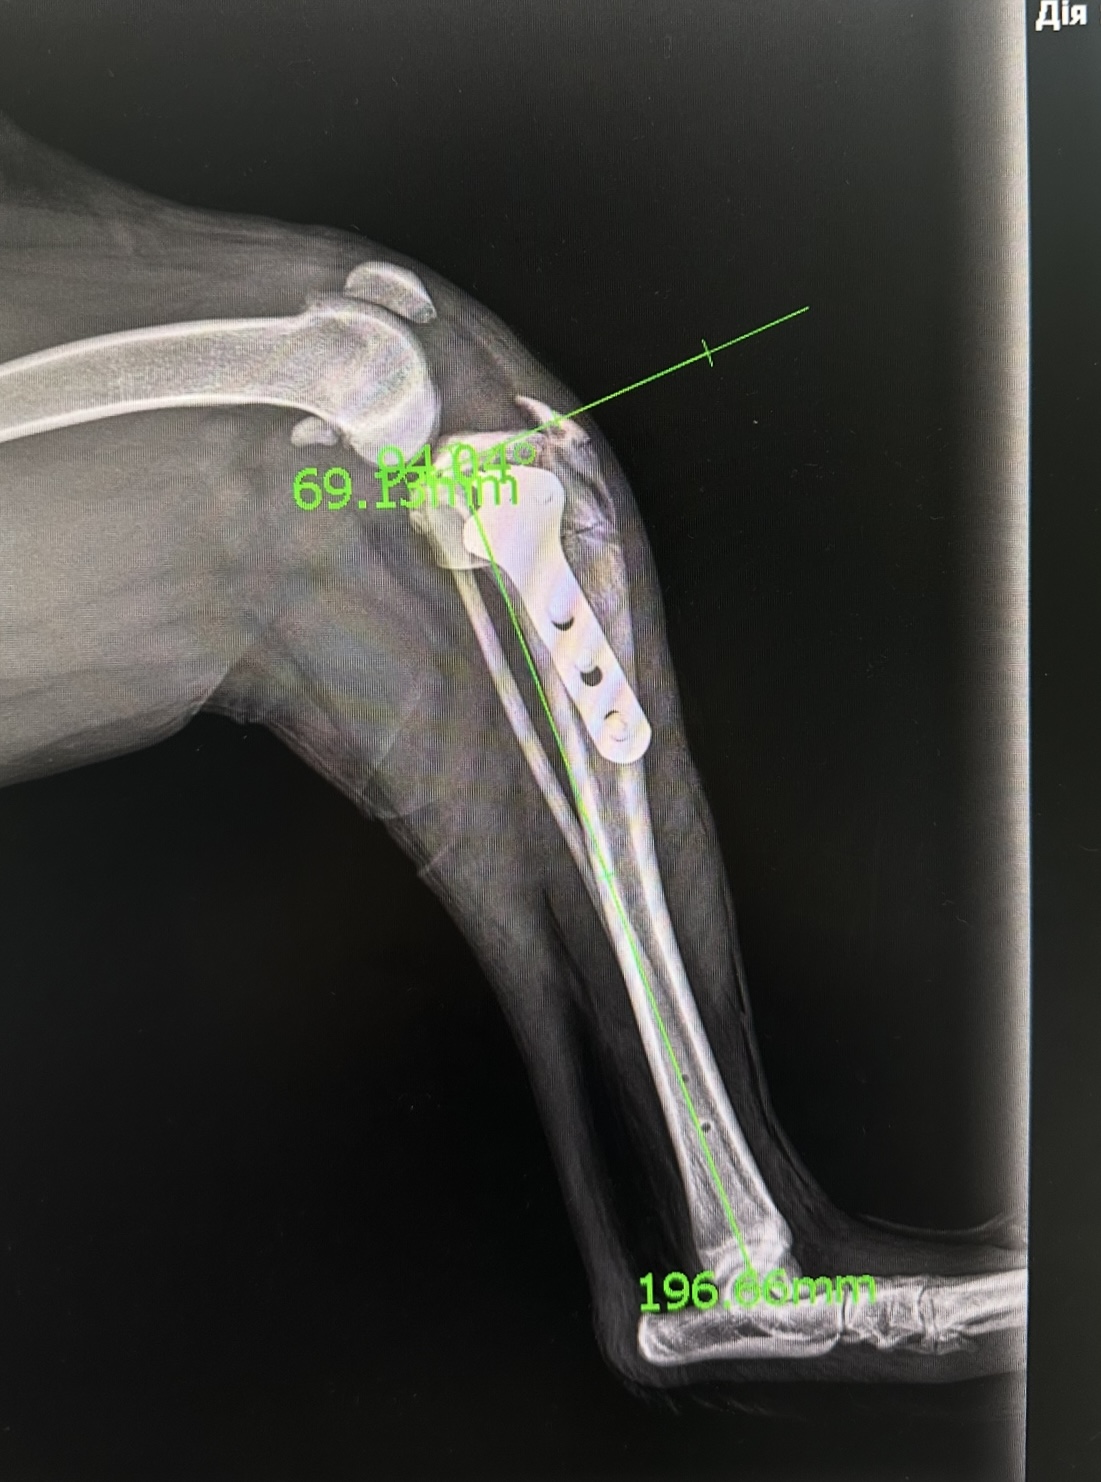

Рентгенографія – метод неінвазивного дослідження внутрішньої структури органів, які проектуються за допомогою рентгенівських променів на спеціальний цифровий перетворювач. Наш рентгенологічний комплекс є одним з найсучасніших систем на території України і видає зображення через 1.5 секунди після знімку що мінімізує час знаходження тваринки на рентген столі, час огляду і саме важливе дозу випромінення яку отримує тваринка і люди навколо, наш сучасний ветеринарний рентген настільки безпечний, що доза опромінення дозволяє без будь яких наслідків для здоров’я робити більше 300 знімків на рік.